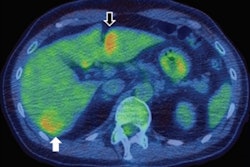

A medical team at Imperial College Healthcare NHS Trust is performing noninvasive MRgFUS thalamic lesioning for essential tremor using Exablate Neuro as part of a trial. The treatment begins with the use of low-energy ultrasound waves under MRI guidance to identify the part of the thalamus and subthalamic region thought to be responsible for causing tremors. Once it's located, high-intensity ultrasound waves are applied to heat and destroy only the target tissue while the patient is fully conscious and lying on the treatment bed in an MRI scanner.